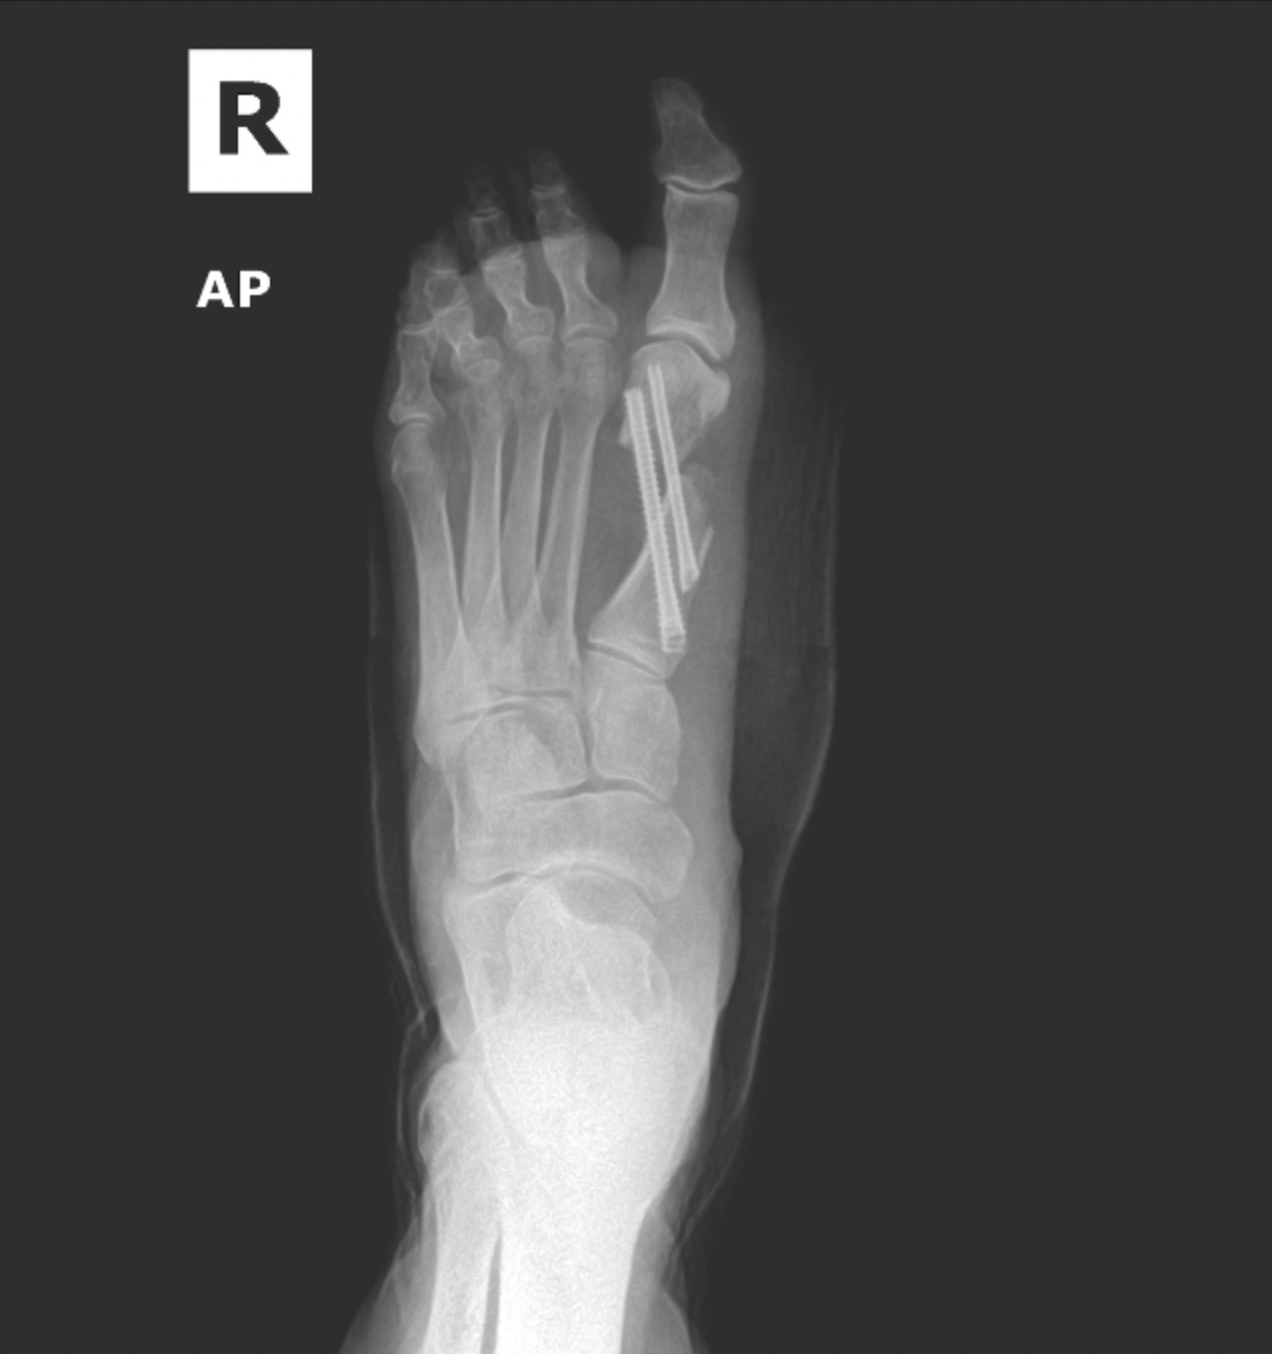

Ankle fracture repair

Pre-op XR Images

Postop XR Images